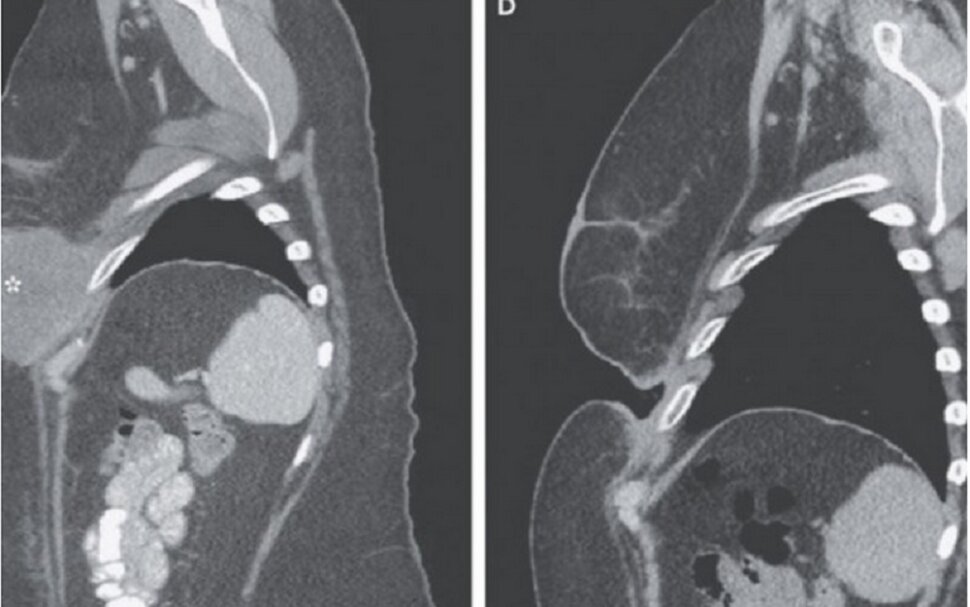

Žena, pacijentica, koja ima 49 godina primila je koktel lijekova u samo jednom tretmanu i njezin tumor nestao je iz prsa te joj ostavio veliku prazninu. Ona je jedna od 150 kliničkih ispitanika u studiji u kojoj su liječnici željeli vidjeti reagiraju li pacijenti na terapiju bolje kad im se daje koktel lijekova ili kad dobivaju svaki lijek pojedinačno.

Dotična pacijentica je primila koktel novih lijekova (Yervoy i Opdivo) za oboljele od karcinoma kože kojima se karcinom proširio i na druge organe.

Pacijentica se s ovim rakom borila četiri godine. Operacijskim putem je ranije izvadila nekoliko tumora te prolazila kroz kemoterapiju, a onda je u samo tri tjedna uspjela izliječiti rak.

Kod čak 53 posto pacijenata u samo tri tjedna tumori su se smanjili za 80 posto, a melanom je nestao kod 22 posto ispitanika do kraja studije i to sve kod pacijenata u 4. stupnju oboljenja.